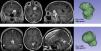

MétodosEstudio observacional retrospectivo unicéntrico de una cohorte de meningiomas sintomáticos intervenidos en el período comprendido entre enero de 2015 y diciembre de 2022. Mediante software de segmentación, para cada meningioma se calculó el denominado factor de superficie (FS), que es un parámetro objetivo que relaciona la superficie de una esfera (figura con la menor área para un volumen dado) de igual volumen que el tumor con la superficie real del tumor. Este cociente varía de 0 a 1, siendo 1 la máxima esfericidad posible. Dado que los meningiomas de forma irregular presentan una mayor superficie en relación con su volumen, su FS tiende a ser menor cuanto más irregular es el tumor. Se correlacionaron los FS con el grado histológico y se evaluó el poder predictivo del FS mediante curva ROC.

MethodsUnicentric retrospective observational study of a cohort of symptomatic meningiomas surgically removed in the time period between January 2015 and December 2022. Using specific segmentation software, the surface factor (SF) was calculated for each meningioma. SF is an objective parameter that compares the surface of a sphere (minimum surface area for a given volume) with the same volume of the tumor against the actual surface of the tumor. This ratio varies from 0 to 1, being 1 the maximum sphericity. Since irregularly-shaped meningiomas present proportionally greater surface area, the SF tends to decrease as irregularity increases. SF was correlated with WHO grade and its predictive power was estimated with ROC curve analysis.